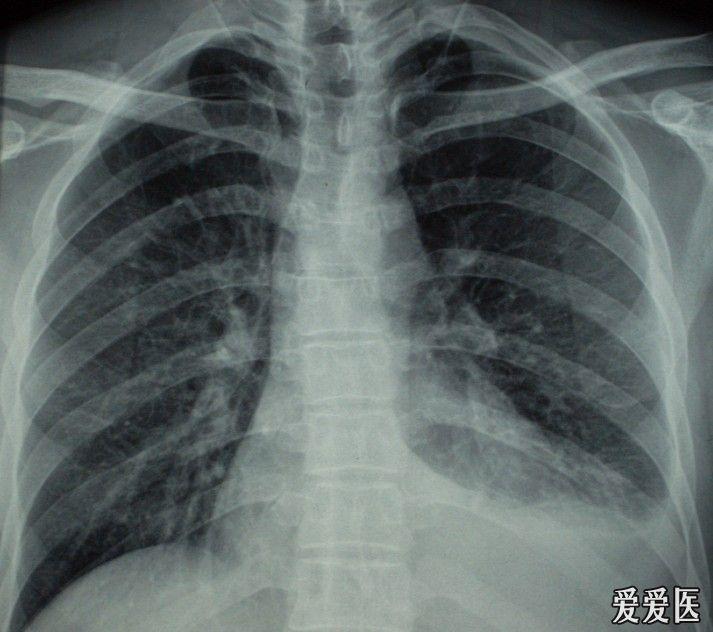

胸片显示胸腔积液.

积液的上缘在第4前肋水平以上,第2前肋水平以下,中下肺野呈均匀致密影

患侧肺野呈均匀致密阴影,肋间隙增宽,纵隔向健侧移位.